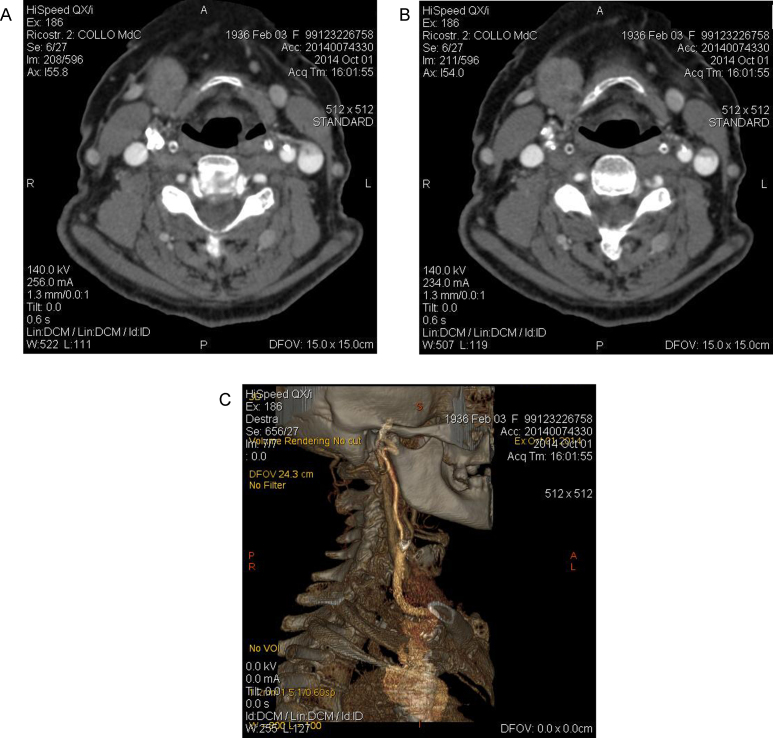

A 78-year-old woman was admitted to undergo coronary artery bypass grafting (CABG) for the elective treatment of triple vessel coronary artery disease (CAD). At preoperative duplex ultrasound scanning of the supraortic trunks (SAT), an asymptomatic, 80% stenosis of the right internal carotid artery (ICA) was detected. The stenosis was confirmed at a spiral CT scan of the SAT (Fig. 1A–C). The contralateral carotid artery presented a hemodynamically non-significant, calcified plaque. The vertebral arteries were equivalent, both injected the basilar artery and did not present hemodynamically significant lesions. The patient was scheduled for combined eversion carotid endarterectomy (CEA) and CABG. The combined carotid and coronary artery revascularization was considered an indication for systematic shunting during CEA [16]. At operation, after exposing the right carotid bifurcation and gently mobilizing the distal ICA, the ICA itself was sectioned at its origin and a Pruitt-Inahara shunt (Le Maitre Vascular Inc., Burlington, MA) was inserted. Immediately after shunt insertion, an intense bleeding was observed from beneath the digastric muscle, due to a 2-mm diameter rutpture of the ICA at the tip of the shunt. The ICA was controlled more distally and the shunt was gently repositioned beyond the lesion. A segment of greater saphenous vein, already harvested for CABG, was tailored to perform a small patch repair of the arterial lesion with the shunt in place (Fig. 2). Eversion endarterectomy completed the procedure, which was followed by CABG. The patient made an uneventful recovery and returned home on postoperative day 12, with a regularly patent ICA revascularization at control duplex ultrasound, performed before discharge from the hospital.

Fig. 1.

Preoperative CT scanning of the supraaortic trunks (SAT) showing an 80% stenosis of the right internal carotid artery at horizontal sections (A,B) and 3-D reconstruction (C).